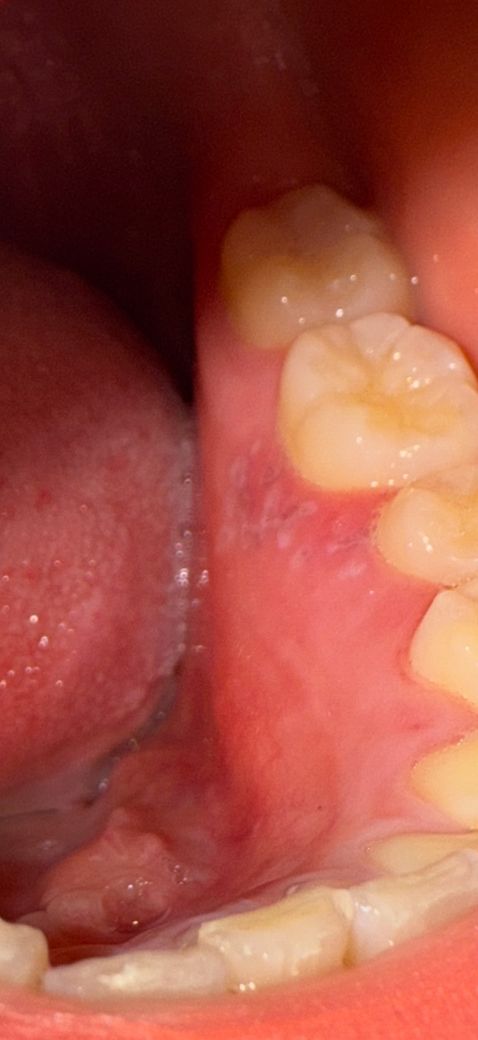

사진은 순서대로 목요일 - 금요일(어제) - 금일오전 - 금일 오후입니다. 처음엔 부어서 살이 울퉁불퉁 올라온 느낌(통증없음), 살짝 하얗게 수포처럼 올라옴 (통증 무), 염증 아문 듯한 빨간 흉터 (통증무), 오늘은 마치 긁힌? 패인? 듯한 염증자국 (혀로 건들면 정말 아주 조금 따끔)

혀로 만져보면 오늘은 실제로도 패인듯한 촉감입니다 ㅜ 네번째 사진에 허옇게 보이는 건 팝콘찌꺼기 일수도 있어요 (방금 먹고 찍었는데 억지로 빼긴 아파서 그대로 찍었어요ㅠ)

• 2번 째 사진